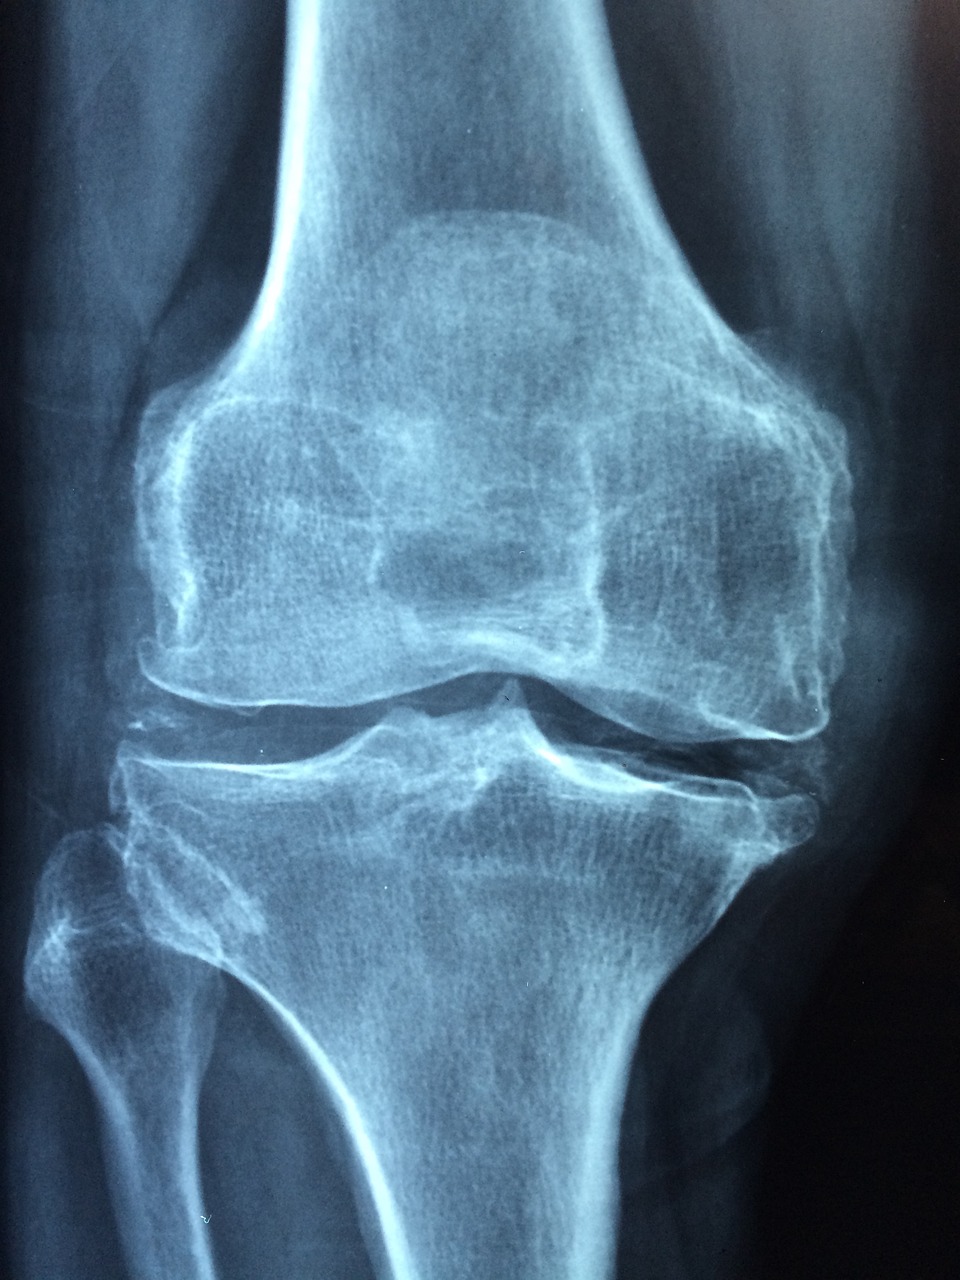

1. 갑작스럽고 강렬한 관절통

갑자기 극심한 관절통, 특히 엄지발가락에 통증이 나타난 적이 있다면 통풍의 특징적인 증상을 접했을 수도 있습니다.

2. 부종과 발적

통풍은 통증에서 그치지 않고 동반자인 부종과 발적을 동반합니다.

요산 결정이 관절에 축적되면 염증 반응을 유발합니다.

해당 관절이 부어오르고 붉은색을 띠는데, 이는 신체가 이러한 미세한 결정의 침입에 반응하고 있다는 신호입니다.

이러한 시각적 신호를 인지하는 것은 통증의 영역을 넘어서는 통풍 증상을 확인하는 데 매우 중요합니다.

3. 제한된 이동 범위

"움직임이 제한된다" 통풍은 종종 영향을 받는 관절에서 제한된 범위의 움직임으로 이어집니다.